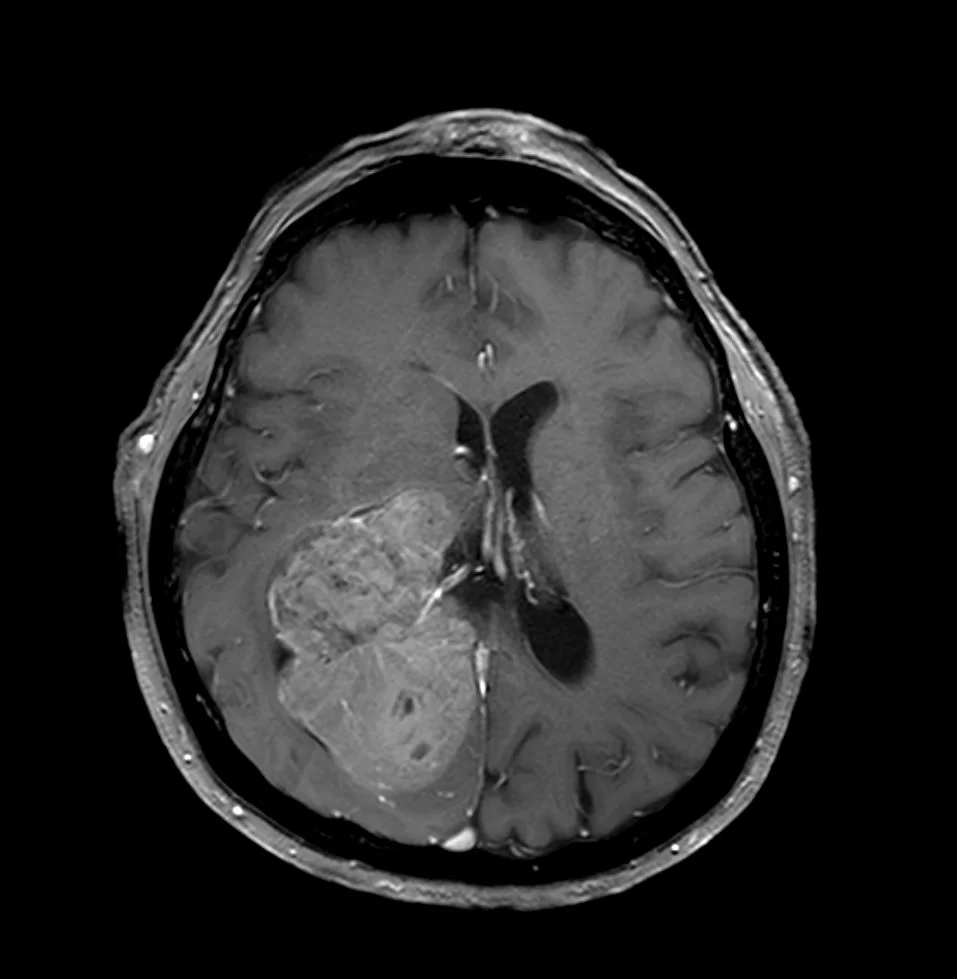

Η μαγνητική τομογραφία ανέδειξε ευμεγέθη χωροκατακτητική εξεργασία εντός της δεξιάς πλάγιας κοιλίας του εγκεφάλου.